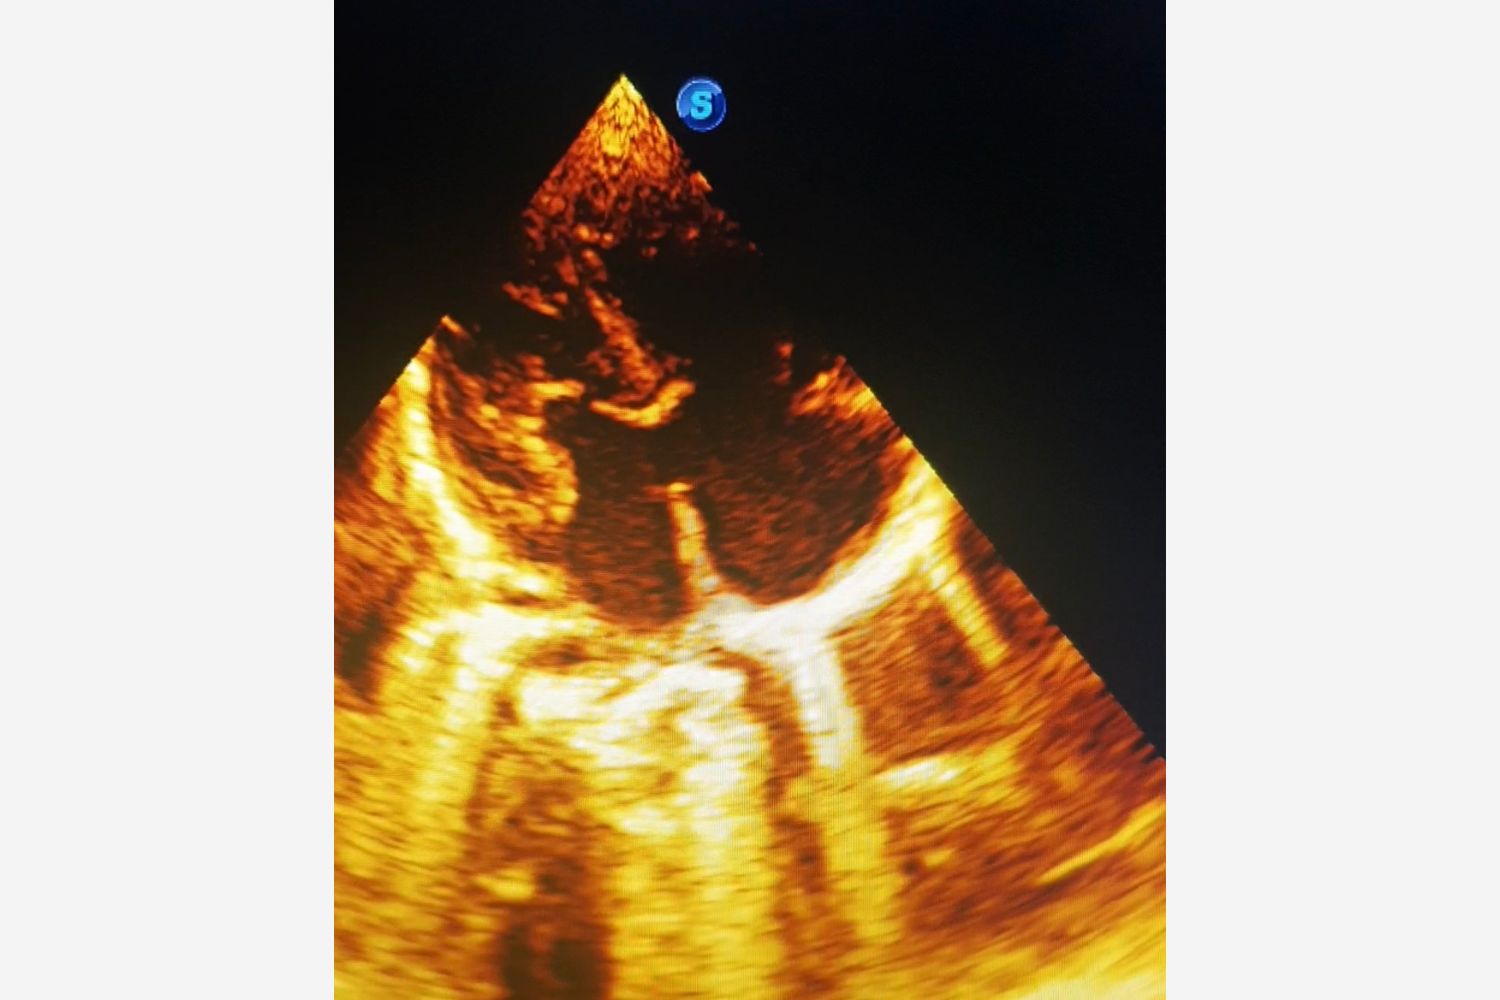

Image of the week 22 April 2026

Image of the week